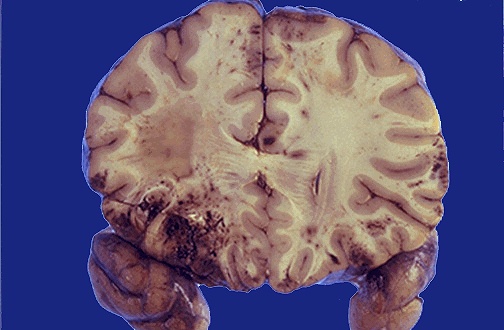

| The lesions seen here are the result of extensive blunt force trauma to the head in a vehicular accident. Mainly the gyri are affected with hemorrhage from contusions and lacerations. [Image contributed by Jeannette J. Townsend, MD, University of Utah] |